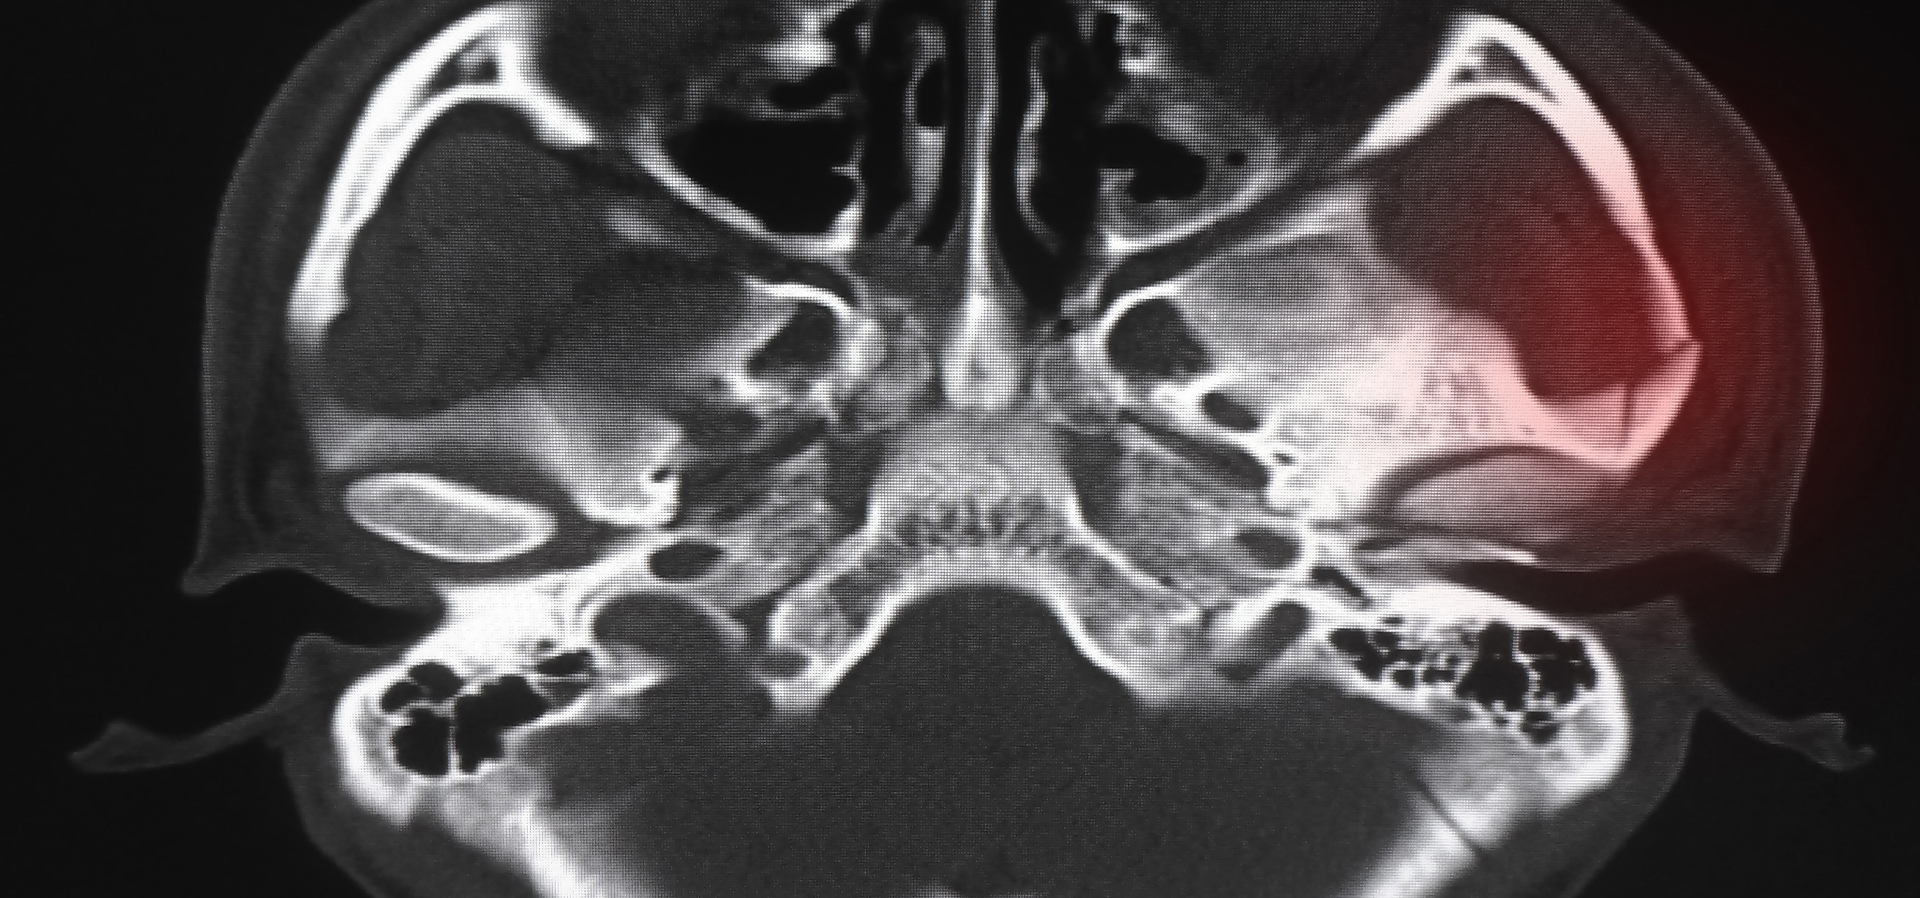

What is an orbital fracture?

An orbital fracture refers to a break or fracture in the bones surrounding the eye socket, known as the orbit. Orbital fractures commonly occur as a result of traumatic incidents, such as car accidents, falls, or sports injuries, where a significant force is applied to the face. These fractures can vary in severity, ranging from small cracks in the bone to complete breaks that cause the bones to become displaced. To find out how Dr. Warner can help you, we welcome you to request a consultation at our practice in Sacramento, CA

What are the signs and symptoms of orbital fractures?

Symptoms of orbital fractures may include swelling, bruising, pain, double vision, difficulty moving the eye, or sunken appearance of the eye. Prompt medical attention is necessary to diagnose and treat orbital fractures, as they can lead to complications such as vision problems or infections if left untreated.

Some orbital fractures do not require repair and can spontaneously heal with no complications. Others require repair using advanced orbital surgery with implants and plating systems to stabilize the fracture allowing it to heal.